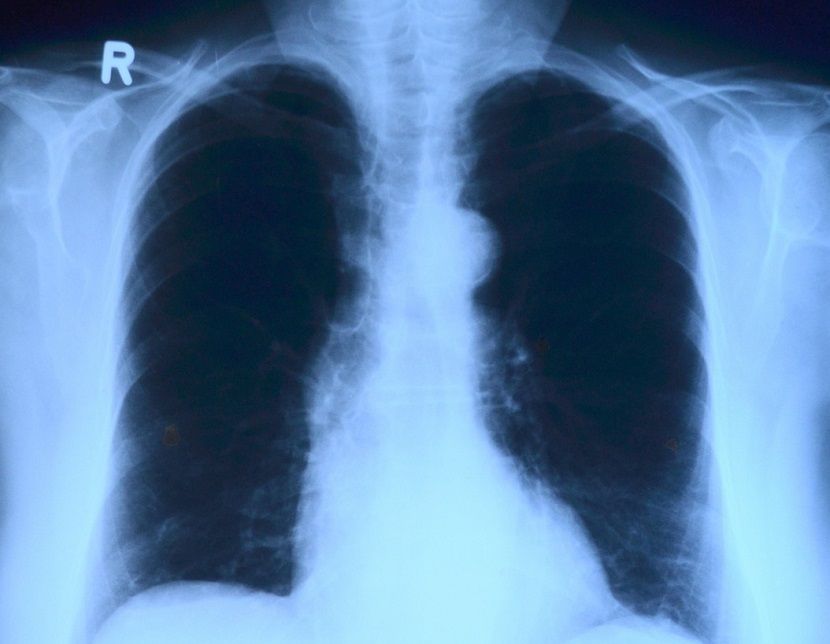

Проведение качественных анализов выявило в Татарстане рост числа вирусных пневмоний. Об этом заявил замглавы Минздрава РТ Владимир Жаворонков.

— В настоящее время 8% от всех пневмоний являются вирусными. В целом этот показатель идет в тренде того, что все пациенты с заболеваниями респираторного тракта стали просматриваться как потенциально подозрительные пациенты, – пояснил Жаворонков.